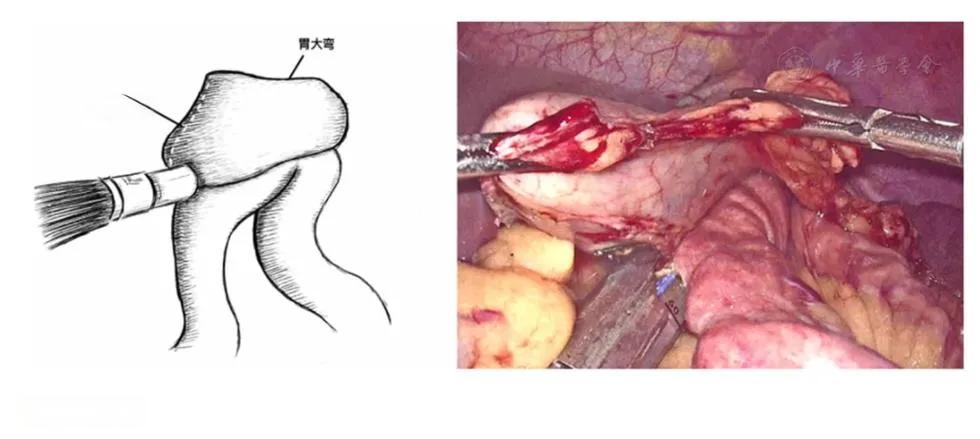

在消化道重建方法中,Billroth I式吻合因其操作相对简单且能保持正常生理结构而被广泛采用。然而,这种吻合方式存在吻合口张力大、易发生吻合口瘘的缺点。为解决这一问题,改良的Overlap吻合技术应运而生。这种技术通过将胃大弯和十二指肠前壁进行侧侧吻合,有效降低了吻合口张力,减少了并发症的发生率。相关研究表明,Overlap吻合在腹腔镜全胃根治术上应用安全可靠,术后并发症的发生率较低,其近、远期疗效优于其他常见的吻合方法。